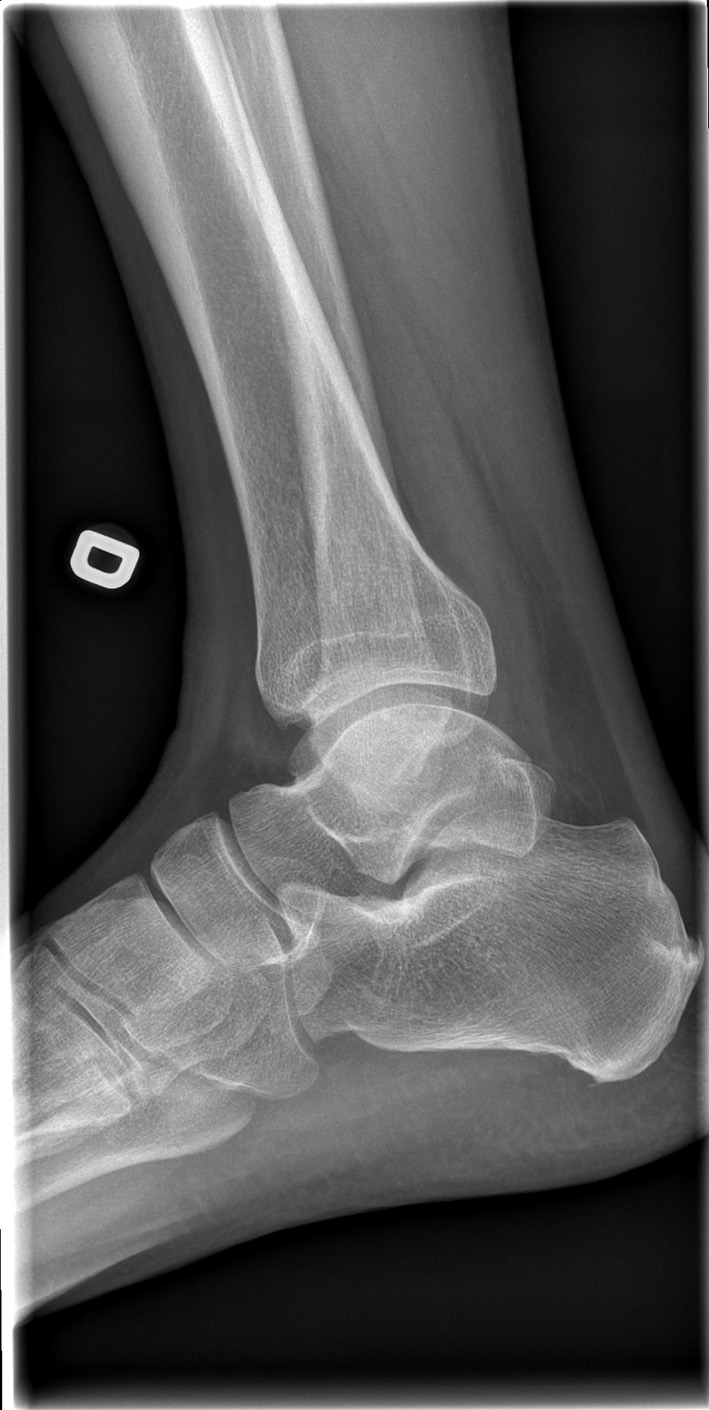

69-year-old male:

Persistent right ankle pain following a sprain.

Enthesopathy

Little enthesopathy on the posterior aspect of the calcaneus.

Plantar fascia enthesopathy

Little plantar fascia enthesopathy on the inferior aspect of the calcaneus.